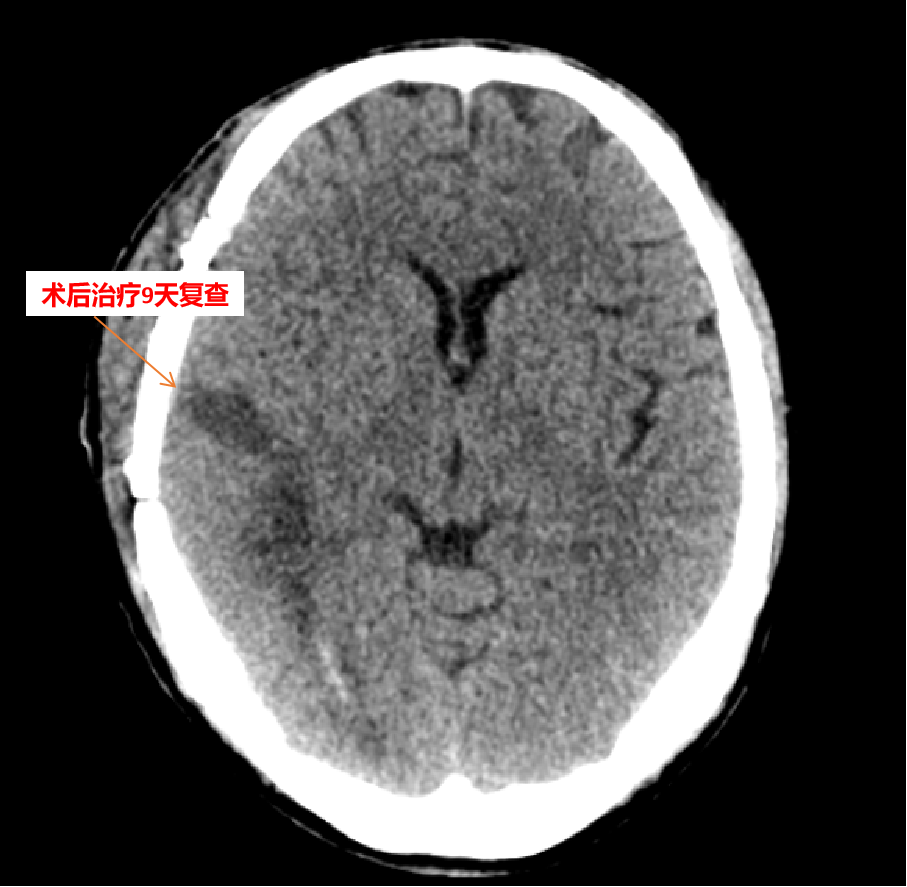

术后经复查颅脑CT后发现脑内血肿清除彻底,而且碎骨片清除彻底,无残屑,为避免术后颅内感染打下了坚实的基础;术后给予有效抗生素预防感染,经反复腰穿证实,无颅内感染。经兰陵县人民医院颅脑创伤外科的积极抢救治疗,病人已抢救成功,目前此患者在兰陵县人民医院继续进行康复治疗。

此例病人的抢救成功,标志着兰陵县人民医院抢救颅脑火器伤的水平提高了一个层次,填补了兰陵县人民医院此项领域的空白,具有划时代的意义!